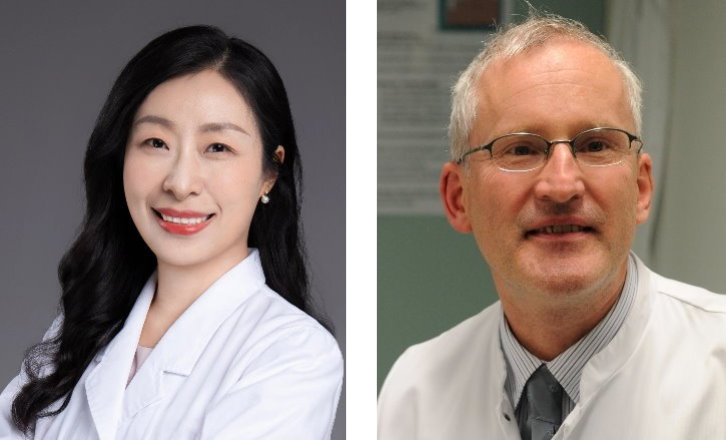

Ultrasonografi kontras (CEUS) adalah bidang yang sangat dinamis dan dalam beberapa tahun terakhir inovasi teknologi telah semakin meningkatkan kualitas gambar. Salah satu inovasi ini adalah ultrasonografi kontras tingkat frame tinggi (HiFR CEUS) yang dapat menghasilkan hingga sepuluh kali lebih banyak gambar dibandingkan ultrasonografi konvensional ŌĆō dalam waktu yang sama. Peneliti di tujuh pusat di Jerman, Swiss, dan Tiongkok sedang mengevaluasi efektivitas HiFR CEUS dalam mendiagnosis lesi hati kecil. Profesor Dr Yi Dong dari Departemen Ultrasonografi, Rumah Sakit Xinhua, Shanghai Jiaotong University School of Medicine, dan Profesor Dr Christoph F Dietrich, Departemen Penyakit Dalam Umum, Hirslanden Bern, Swiss, menjelaskan latar belakang dan tujuan dari studi ini.

Profesor Dong Yi, MD, PhD adalah Kepala Departemen Ultrasonografi di Rumah Sakit Xinhua, Shanghai Jiaotong University School of Medicine. Ia menjabat sebagai Wakil Ketua Komite Pemuda, Chinese Society of Ultrasound in Medicine (CSUM) dan Shanghai Society of Ultrasound in Medicine. Sebagai anggota Kelompok Ahli Pedoman dan Praktik Klinis yang Baik, ia ikut menulis rekomendasi untuk ultrasonografi kontras (CEUS) pada hati (diperbarui 2020) untuk WFUMB bekerja sama dengan EFSUMB, AFSUMB, AIUM, dan FLAUS. Dong Yi adalah peneliti postdoctoral di Massachusetts General Hospital, Harvard Medical School, USA, dan peneliti di Universitas Pavia, Italia, dan di Rumah Sakit Caritas, Bad Mergentheim, Jerman.

Profesor Dr. med. Christoph Frank Dietrich, MBA, adalah kepala Departemen Medis di Hirslanden Kliniken Beau Site, Salem dan Permanence, Swiss. Ia adalah Profesor honoris causa di Universitas Zhengzhou, Tiongkok. Ia memiliki spesialisasi dalam penyakit dalam (1997), gastroenterologi & hepatologi (2000) termasuk Fellowship in Gastroenterology (EBG), pneumologi (2002), hematologi dan onkologi (2008), proktologi (2009), kedokteran perawatan paliatif (2009), dan kedokteran geriatri (2009). Ia menjabat sebagai Sekretaris Kehormatan EFSUMB dari 2007 hingga 2011. Ia adalah Presiden European Federation of Societies in Ultrasound Medicine and Biology (EFSUMB, 2013-2015) dan Wakil Presiden World Federation of Ultrasound in Medicine and Biology (WFUMB) dari 2017 hingga 2019. Karir akademisnya berfokus pada endoskopi dan ultrasonografi. Ia telah menerbitkan lebih dari 1100 makalah ilmiah dan bab buku.